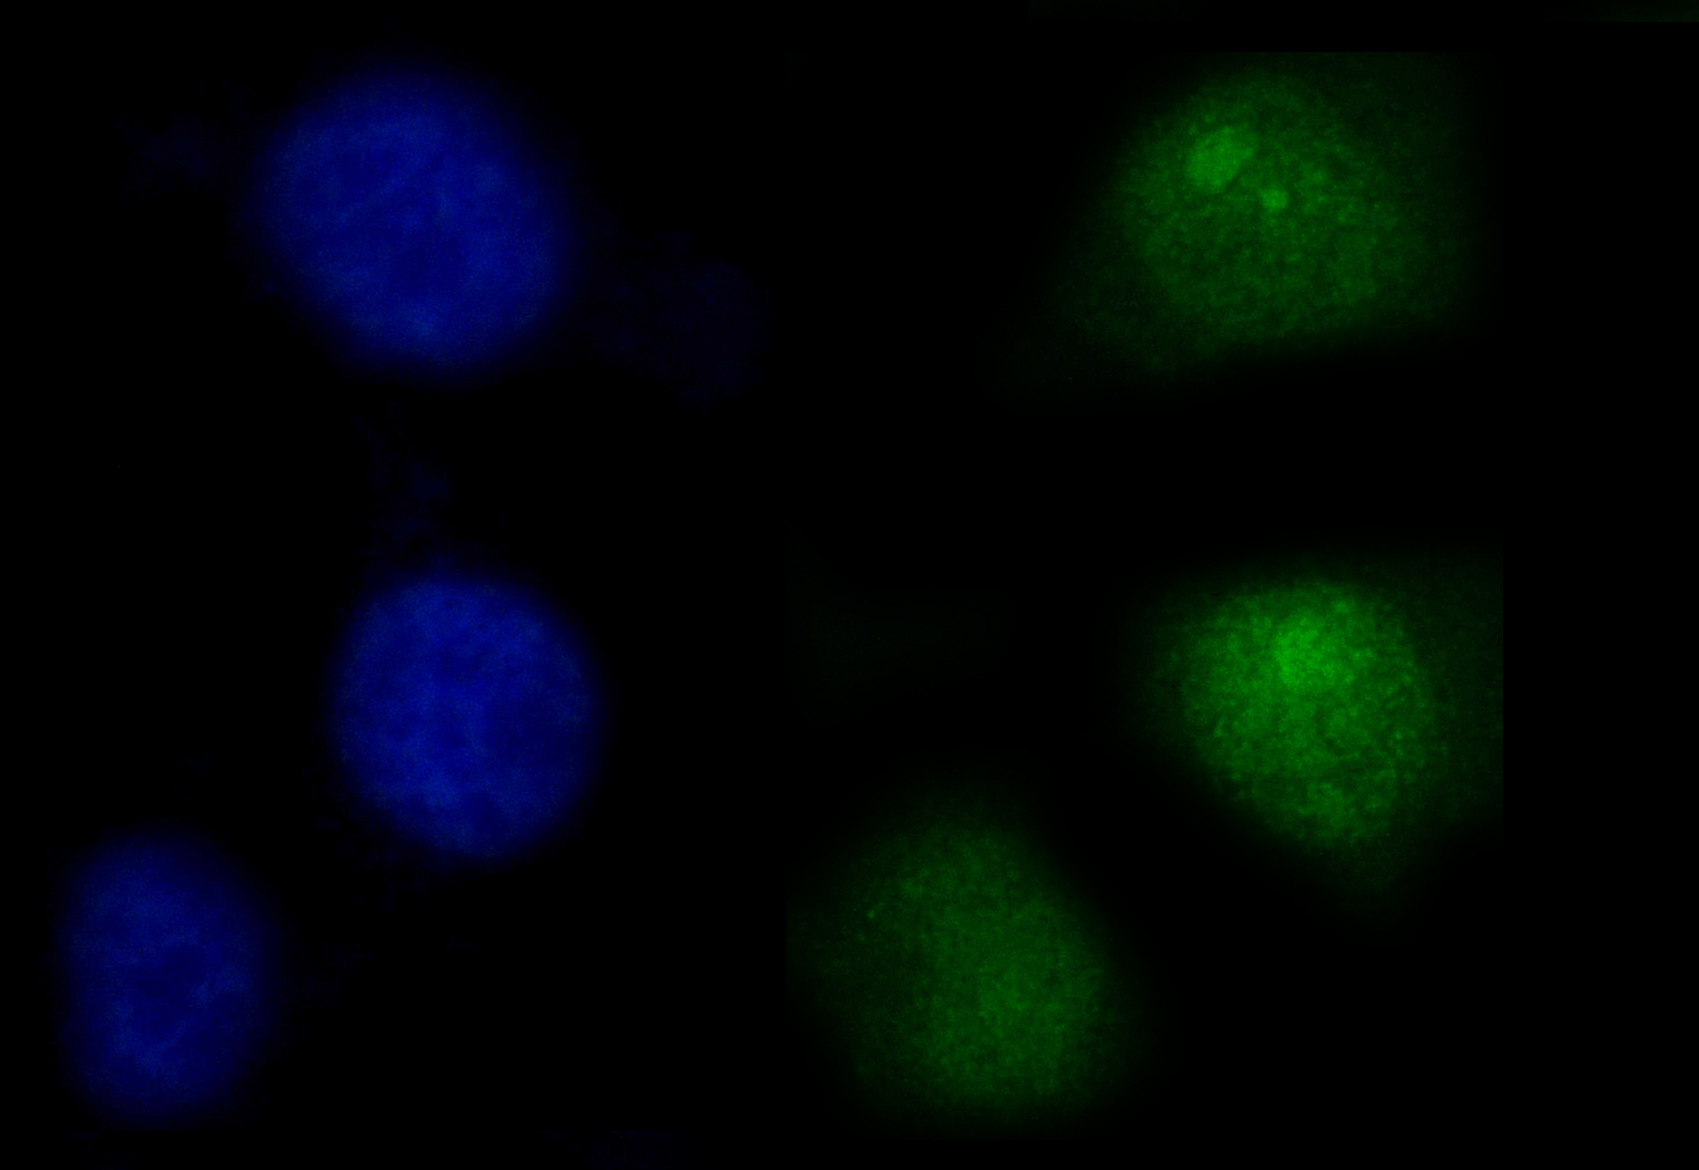

IF analysis of PTPN6 using anti-PTPN6 antibody (M00938-2).

PTPN6 was detected in an immunocytochemical section of A549 cells. The section was incubated with mouse anti-PTPN6 Antibody (M00938-2) at a dilution of 1:100. Dylight488-conjugated Anti-mouse IgG Secondary Antibody (green)(Catalog#BA1126) was used as secondary antibody. The section was counterstained with DAPI (Catalog # AR1176) (Blue).